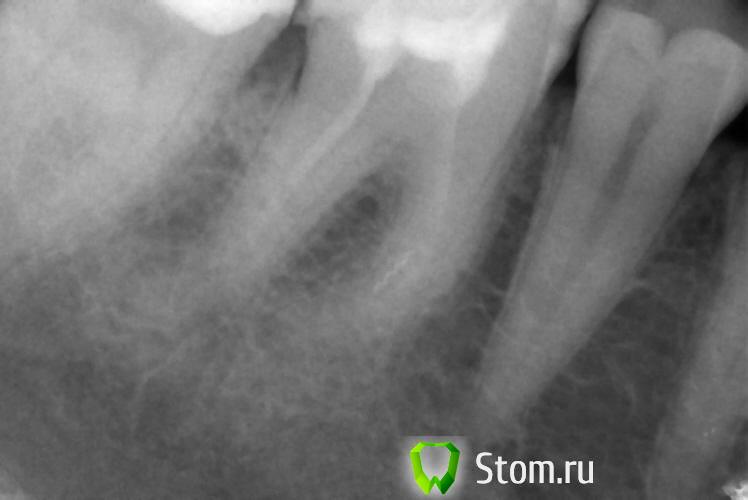

x3m Опубликовано 9 февраля, 2012 Поделиться Опубликовано 9 февраля, 2012 это снимки после лечения каналов?? Ссылка на комментарий

beshdr Опубликовано 9 февраля, 2012 Автор Поделиться Опубликовано 9 февраля, 2012 Да. Ссылка на комментарий

pawa Опубликовано 9 февраля, 2012 Поделиться Опубликовано 9 февраля, 2012 Однокорневые вкладки не проблема, пломбировка корневых каналов неудовлетворительная. Ссылка на комментарий

beshdr Опубликовано 13 февраля, 2012 Автор Поделиться Опубликовано 13 февраля, 2012 Всегда любая отрасль идет по пути наращивания прибылей - стоматология не исключение - и если теперь используют такие материалы, которые через 10 лет рассасываются в канале и требуют повторной перепломбировки - значит скоро будут использовать те, которые рассасываются через 5. Мои каналы я делала 10 лет назад, тогда мне их заделали какой-то пастой на основе цемента и фактически уже тогда зубы были подготовлены к протезированию, причем без всяких корневых вкладок! Сейчас, чтобы распломбировать по 1 каналу в каждом зубе - терапевту потребовался 1 час времени! Реально, там все окаменело. Думаю, эта паста никуда не должна рассосаться, на снимках, возможно, это не так хорошо видно, как если бы каналы были запломбированы гуттаперчей. В общем - всячески себя утешаю, надеюсьь и верю в то, что все будет хорошо и все сделано правильно. Сколько зубов - столько и мнений ))) Ссылка на комментарий